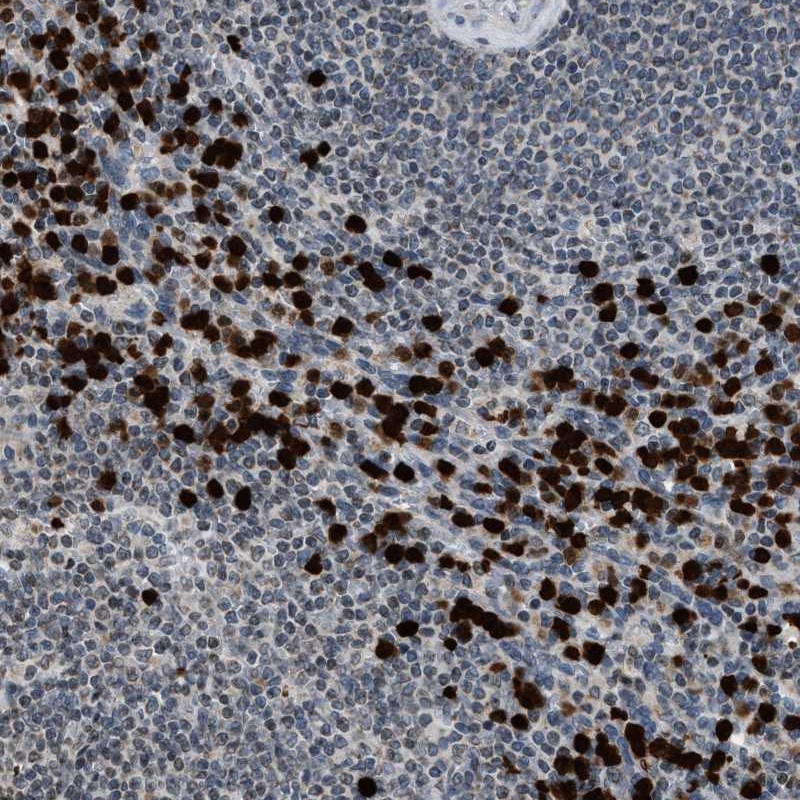

Immunohistochemical staining of human spleen shows strong nuclear and cytoplasmic positivity in cells of the red pulp.